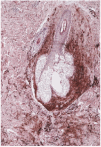

Se practicó una biopsia de la lesión, incluyendo uno de los nódulos profundos, en la que se halló la dermis salpicada por numerosos acúmulos irregulares de melanocitos fusiformes ricos en pigmento y melanófagos, tanto entre los haces colágenos esclerosos de la dermis reticular como en la dermis adventicial perifolicular (figs. 2 y 3).

Fig. 2.--Aspecto histológico a pequeño aumento (hematoxilina-eosina, 20x).

Fig. 3.--Detalle histológico de la lesión que muestra afectación perifolicular (hematoxilina-eosina, 80x).